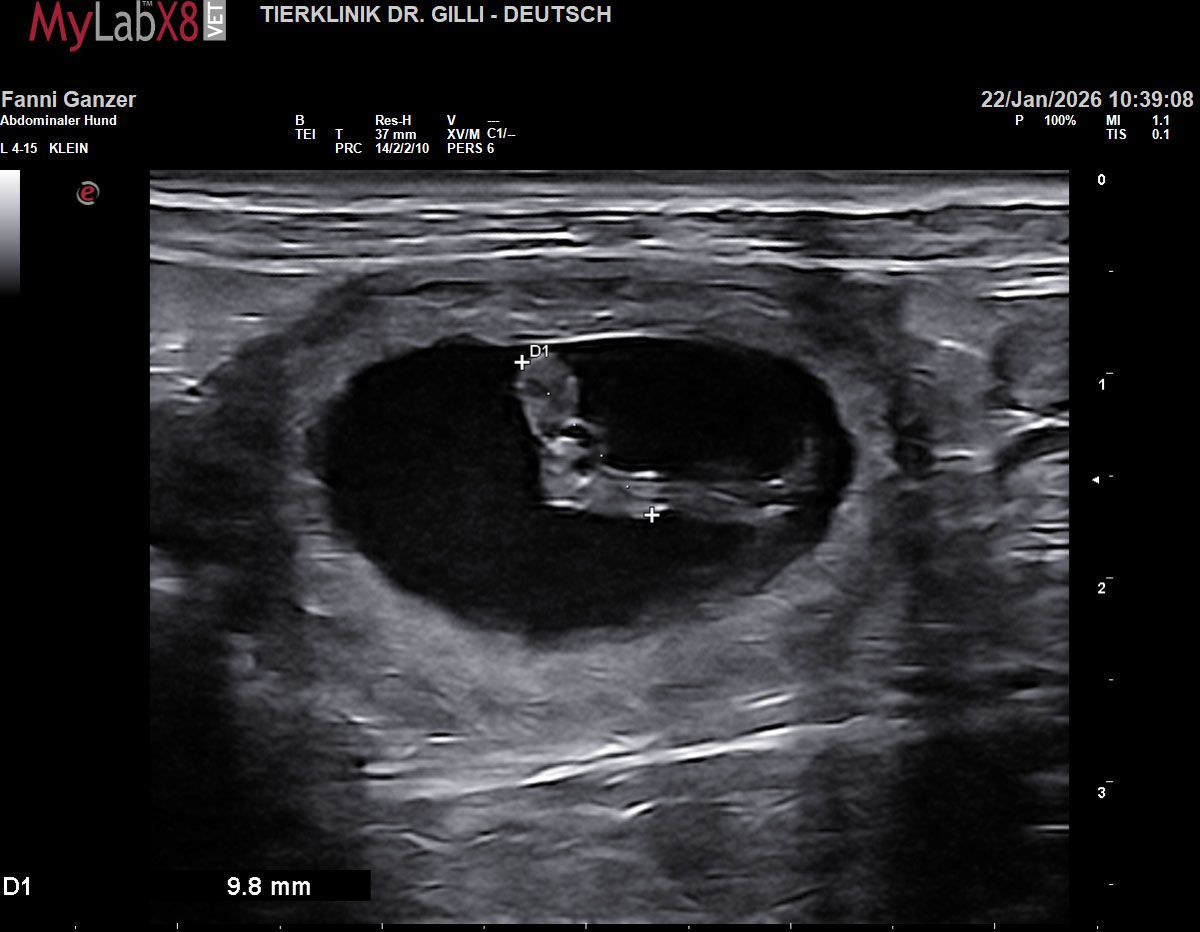

Unser gemeinsamer Ausflug nach Venedig zum Jahresende trägt nun buchstäblich Früchte. Beim Ultraschall konnten wir bereits 3 bis 4 kleine, gefüllte Fruchtblasen zählen. Wie bei jedem Wurf unserer Zucht ist die Aufregung im Hause Of Green Spirits riesig. Wir blicken voller Vorfreude auf die kommenden Wochen und können es kaum erwarten, die nächste Generation unserer Welpen gesund und munter bei uns willkommen zu heißen.